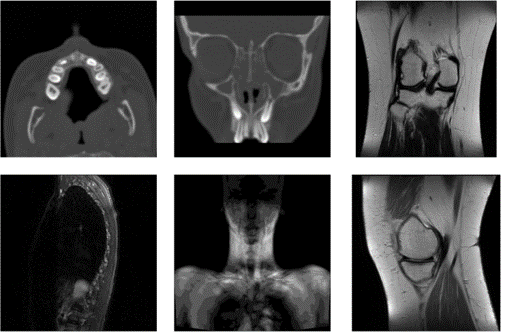

Kompresija slika bez gubitaka je važna u slučajevima kada je akvizicija slika skupa, bilo zbog zakonskih ograničenja, bilo zbog mogućeg gubitka vrijednih informacija. Kompresija medicinskih slika bez gubitaka je posebno značajna kako bi se očuvala dijagnostička upotrebljivost slika

Kolekcija medicinskih slika